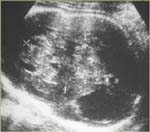

Echographiquement : Masse très échogène occupant plus d’un hémisphère cérébral

Ventriculomégalie controlatérale (VL, V3)

Crâniomégalie